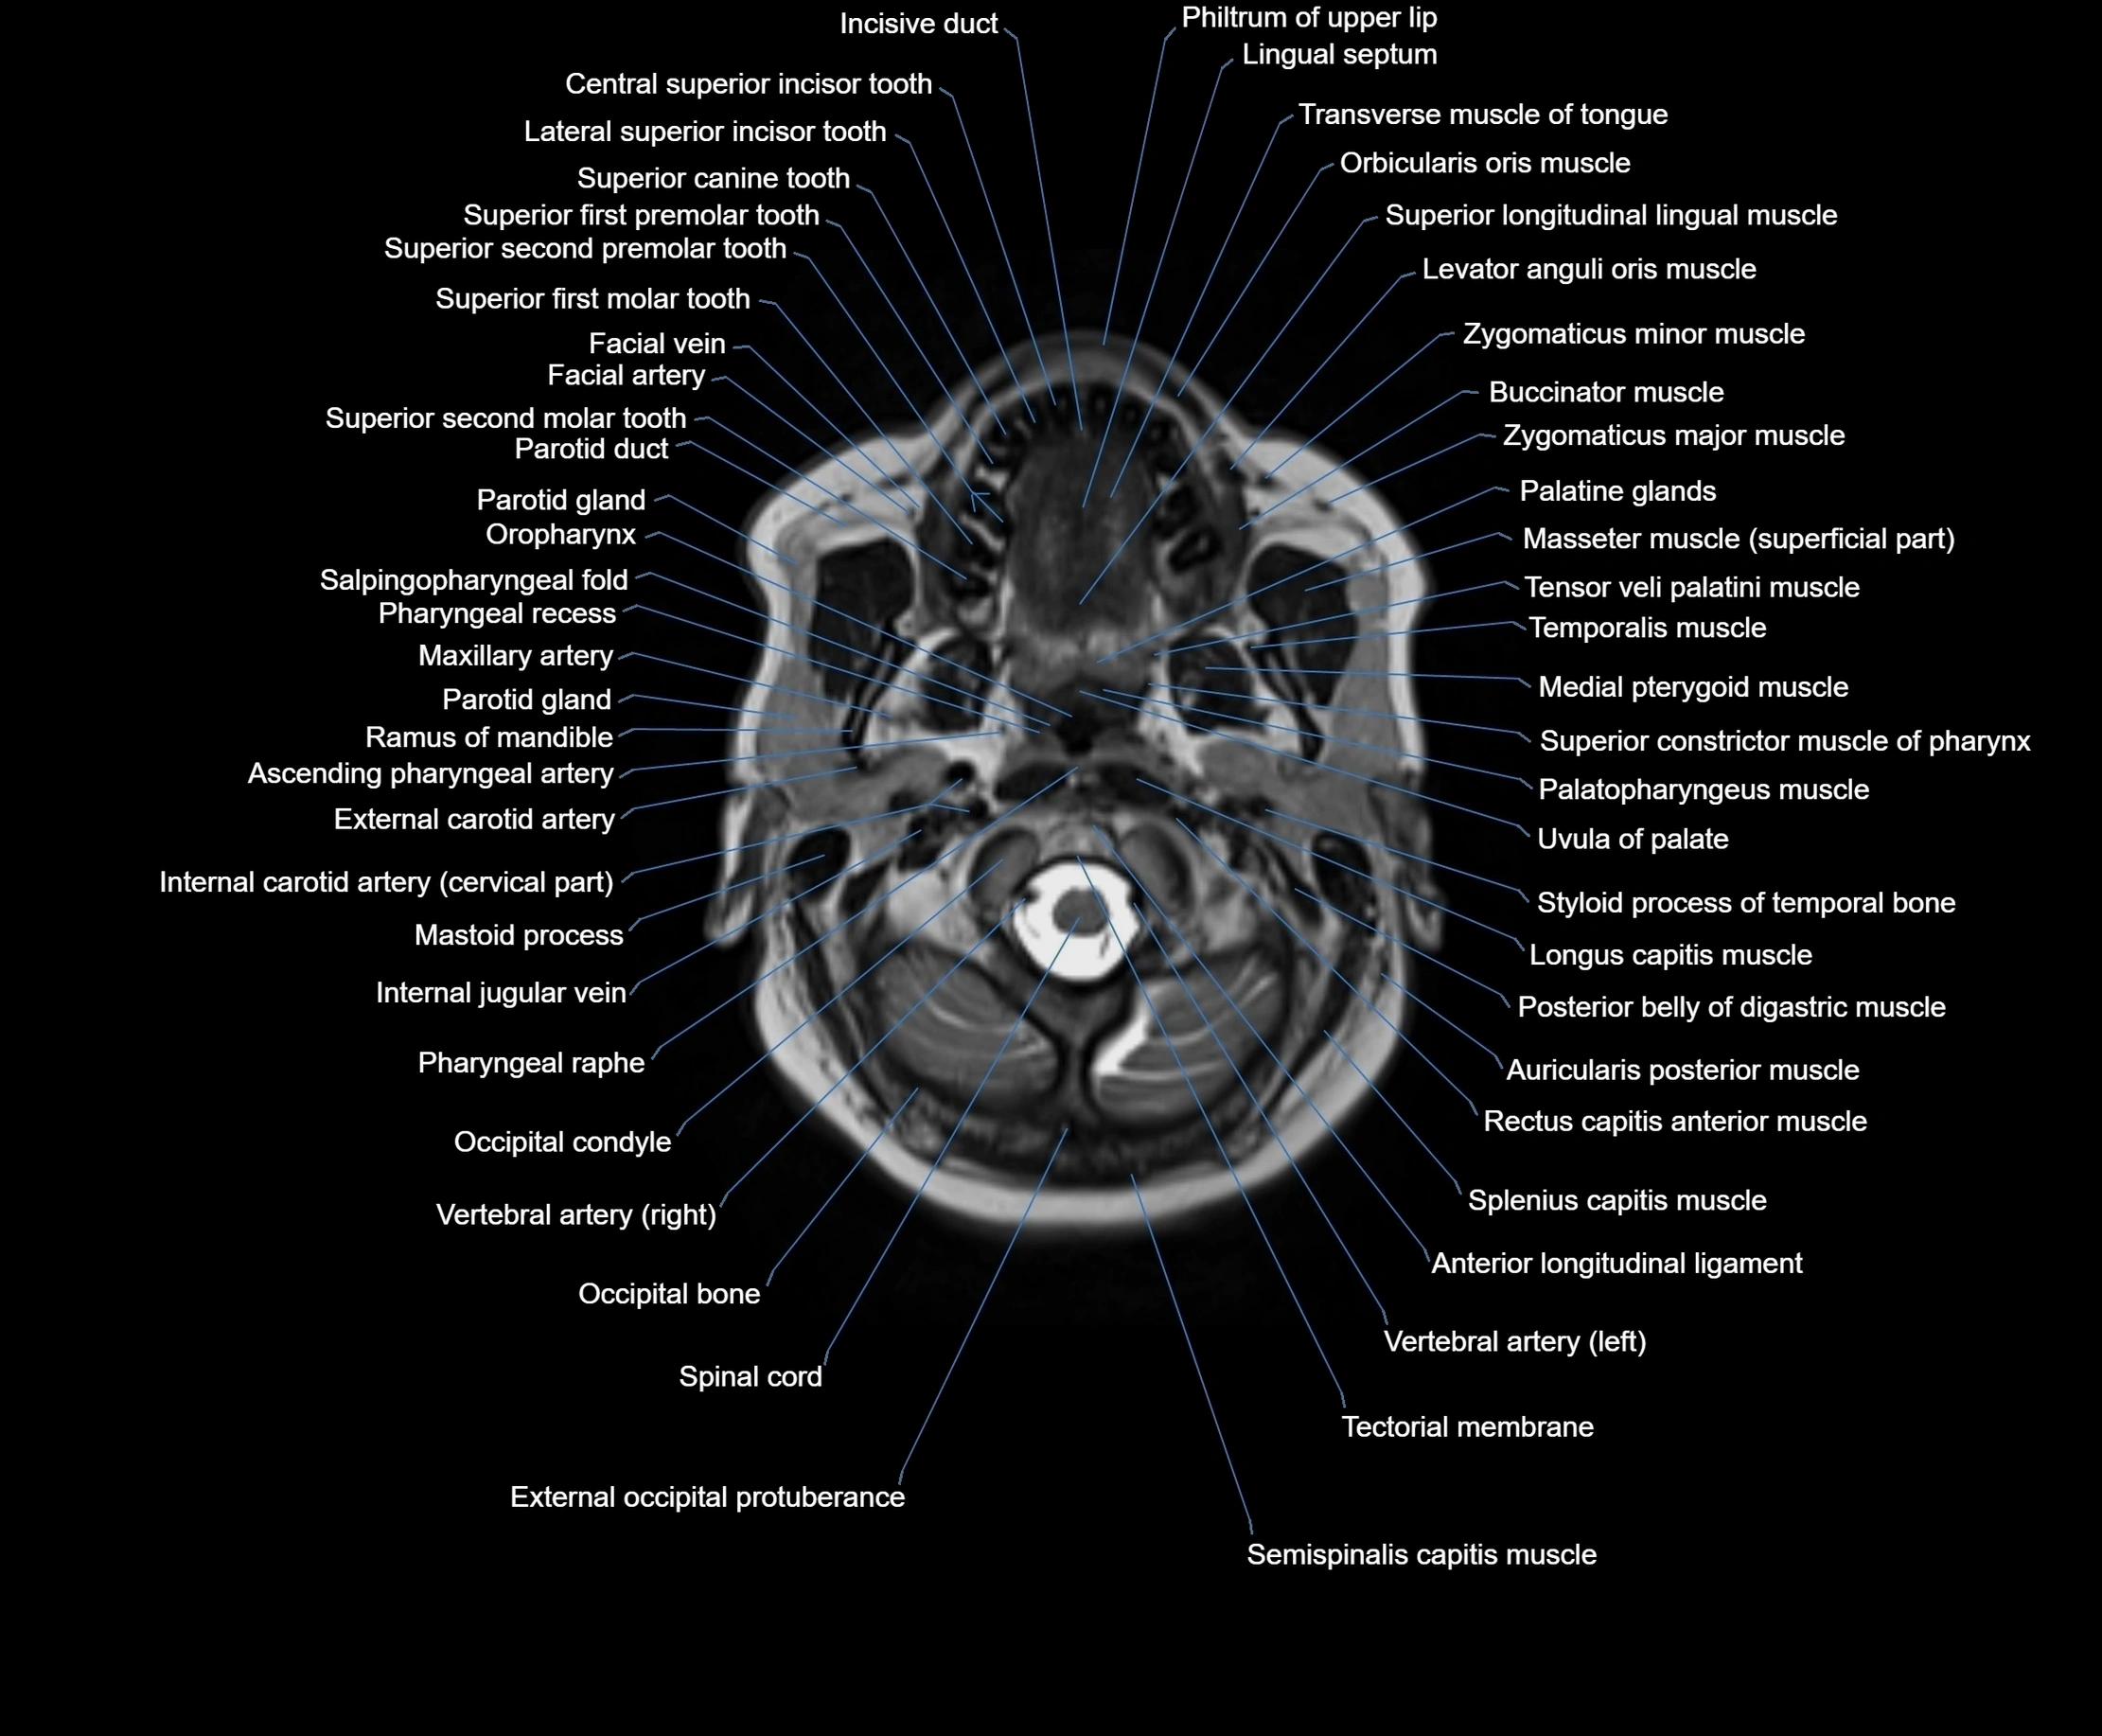

MRI images